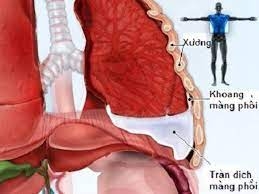

- Tràn dịch màng phổi không rõ nguyên nhân.